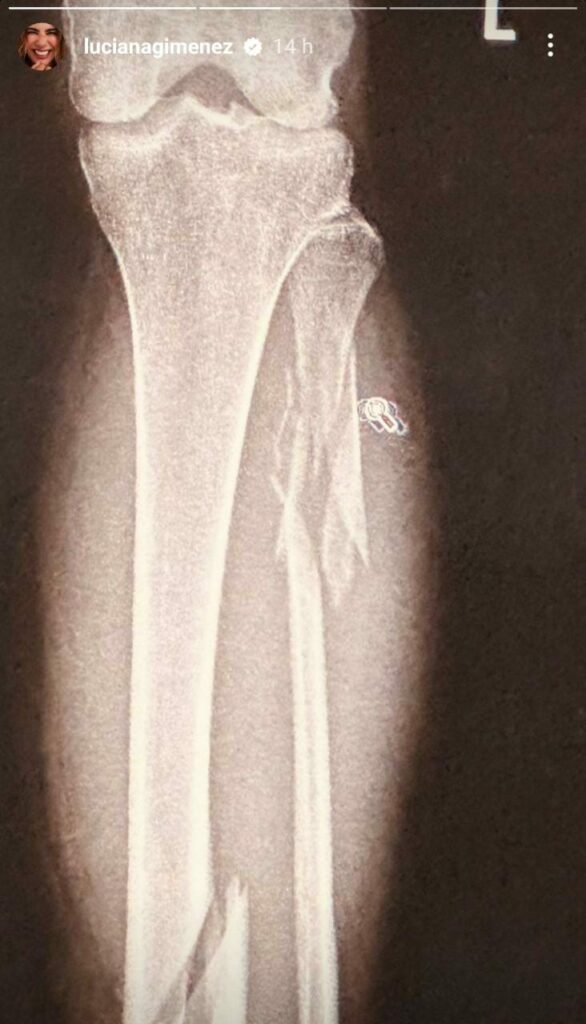

Nos últimos dias, Gimenez passou por uma cirurgia, após ter fraturado sua perna em quatro lugares diferentes em um acidente. mesmo de alta, nas próximas seis semanas, ela continuará a fazer sessões de fisioterapia e deverá evitar voos longos.

“Cada dia é um dia e hoje tem sido bem difícil, pois as dores continuam. A medicação tem ajudado a suportar, mas só quem passou por isso entende a dor e o incômodo que é colocar pinos e parafusos no corpo”, reclamou Gimenez